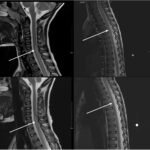

Gait disturbances in pediatric patients can be wrought with diagnostic pitfalls given the broad infectious, traumatic, musculoskeletal, and neurological etiologies. Furthermore, children can have difficulty communicating their pain and can be hard to examine. This case highlights the importance of slowing down to obtain a detailed history as well as perform a thorough exam in our pediatric patients, which can be challenging in a busy emergency department. We present a case of acute transverse myelitis (ATM) in a four-year-old male who presented with a one-day history of limp and bilateral leg pain with weight bearing. The caretakers reported a possible remote trauma from roughhousing at daycare. Neurological examination revealed significant abnormalities including bilateral patellar hyperreflexia, bilateral lower extremity weakness, clonus, and gait ataxia. A brain and spinal MRI revealed longitudinally extensive ATM with cord edema. Despite the lack of any evidence of infectious prodrome, cerebrospinal infectious analysis revealed Mycoplasma pneumonia as the causative agent. Treatment with intravenous (IV) methylprednisolone and azithromycin therapy led to eventual resolution of all neurological sequelae within a few weeks of discharge. This report emphasizes the importance of considering ATM in the differential of pediatric patients presenting with gait complaints, as well as the importance of a thorough neurologic exam, without which the diagnosis would have been missed.